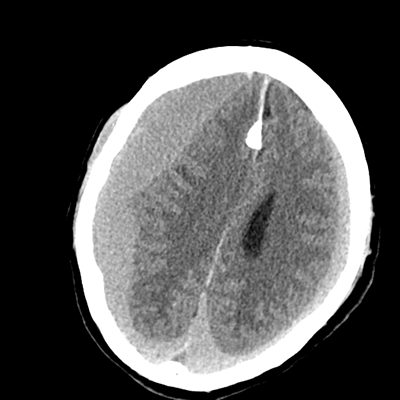

In the ED, initial vitals are notable for BP 118/68, HR 75, SpO2 97%, T37.4C. He was sent to the scanner for a pan-scan. His non-contrast head CT is shown. The ED consults you. They note that he's awake and hemiparetic. You make your way to the ED from the other side of the hospital.

NCHCT

NCHCT 1/15 1/15

NCHCT 2/15 2/15

NCHCT 3/15 3/15

NCHCT 4/15 4/15

NCHCT 5/15 5/15

NCHCT 6/15 6/15

NCHCT 7/15 7/15

NCHCT 8/15 8/15

NCHCT 9/15 9/15

NCHCT 10/15 10/15

NCHCT 11/15 11/15

NCHCT 12/15 12/15

NCHCT 13/15 13/15

NCHCT 14/15 14/15

NCHCT 15/15 15/15

What do you make of his head CT?

The most overt abnormality is the right holohemispheric extraaxial blood; it's subdural in location. The density there suggests that this is an acute finding, fitting the clinical history. There's leftward midline shift as a result, with effacement of the right lateral ventricle. The left side also has a holohemispheric SDH, though smaller in thickness. However, on this side, the SDH is layering, with more isodense blood anteriorly. This suggests that, on this left side, his SDH is acute-on-chronic.

Aside from these obvious extraaxial abnormalities, there's another subtle finding. The patient is known to have had a prior head CT when he had his initial fall a few weeks ago, with the report noting that there was diffuse cerebral volume loss. At his age, we'd expect to see more sulcation. We don't. He doesn't because these hematomas are compressive and he's developed a little cerebral edema as well.